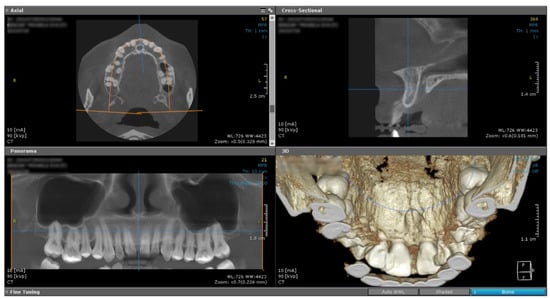

At the clinical exam, the lesion had a shape of a droplet, well delimited, with a dimension of approximately 15 mm (sagittal plane)/10 mm (transverse plane), with a nodular lower pole located at the median palatal fibromucosa, extended between the bilateral palatal rugae. It had a pink tint, smooth surface and soft, resilient and depressible consistency. The upper pole of the lesion was located interdentally between the superior central incisors (1.1–2.1, using the FDI Dental Numbering System, or 8–9, using the Universal Dental Numbering System). On the buccal side of the alveolar crest, the lesion was in contact with the crestal insertion of a hypertrophic upper labial frenulum, having a reddish color and a slightly firmer consistency, apparently fixed to the underlying bone (Figure 1).

The clinical examination also revealed a dentoalveolar incongruence with the presence of a maxillary interincisal diastema of 2 mm and a slight distal tipping of the right upper central incisor, with delicate coverage, that might be associated with the presence of the mentioned lesion. Furthermore, a median buccal gingivo-mucosal scar presented between the two upper central incisors, 1.1/8–2.1/9. The patient affirmed a previous surgical intervention for a frenoplasty of the upper labial frenulum, 3 years before the current hospital presentation, conducted in a private dental office, with intension to correct the diastema, which had no benefits.

Figure 1. Intraoral aspect: (a) aspect of the lesion at the level of the incisive papilla and anterior palatal fibromucosa; (b) aspect of the lesion (buccal view), interincisal diastema and gingivo-mucosal scar.